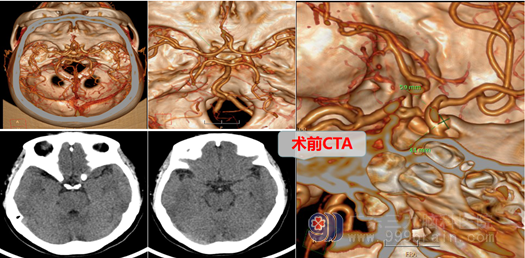

黄阿姨在5年前就间断出现头痛,呈阵发性,偶有头晕,无明显恶心呕吐、四肢抽搐等不适,休息后可缓解,当时一直以为是过度劳累引起的,因此未引起黄阿姨及其家属的重视。近5年来黄阿姨头痛反复发作,曾到当地医院就诊,查头颅MRA提示左侧颈内动脉眼段外缘中型宽颈动脉瘤,近一周黄阿姨头痛加重,严重时黄阿姨连站立都很困难,黄阿姨家属为进一步检查及治疗遂来到广东最大的脑专科医院-三九脑科医院就诊,,神经外十科门诊拟“左侧颈内动脉眼段动脉瘤”收住院。

颅内动脉瘤对病人生命是一个巨大威胁,有“不定时炸弹”之称,因为它会不会破裂(爆炸),什么时候破裂,谁也不知道,它一旦破裂就会造成颅内大出血,直接威胁生命的危险。故一旦发现脑动脉瘤,一般都要进行介入或手术治疗。颈内动脉眼段动脉瘤由于载瘤动脉位置低,靠近颅底,瘤颈位于前床突骨质内下方,故直接开颅手术夹闭难度很大,要磨除部分骨质才可能暴露瘤颈。

在完善相关检查后,外十科主任欧阳辉教授组织进行了详细的术前讨论,邓心情医师向家属交待了病情,说明手术的必要性和手术风险,在取得病人及其家属理解并签字同意后,外十科团队在全麻下为黄阿姨进行了左侧颈内动脉眼动脉段动脉瘤夹闭术。全麻成功后,取左侧翼点入路,咬除部分蝶骨嵴,从硬膜外细心暴露并磨除前床突,再剪开硬膜,在高清显微镜下释放侧裂池脑脊液,显露左颈内动脉、视神经,在床突段可见宽颈囊性动脉瘤,锐性分离动脉瘤周围粘连,暴露并保护动脉瘤,充分显露动脉瘤颈后精准地用动脉瘤夹将其夹闭,检查周围动脉保护完好,载瘤动脉通畅。手术顺利,麻醉满意,出血不多,术后病人全麻清醒,安返病房。